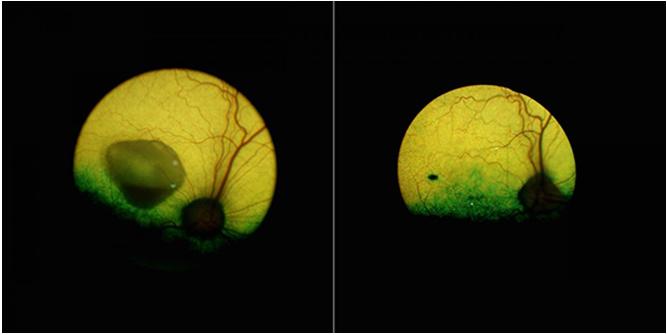

卵黄状黄斑变性犬的眼睛,左侧是未治疗的,右侧是基因治疗5年后的。来源:宾夕法尼亚大学

更令人鼓舞的是,经过治疗的狗狗的眼睛在长达5年的时间里都没有疾病。这种基因疗法在狗身上是有效的。“在分子水平上,我们证实了犬类和人类的BEST1基因都能纠正RPE-PR复合物的位置,并能够恢复这个要害接口的细胞结构”,Cideciyan说。